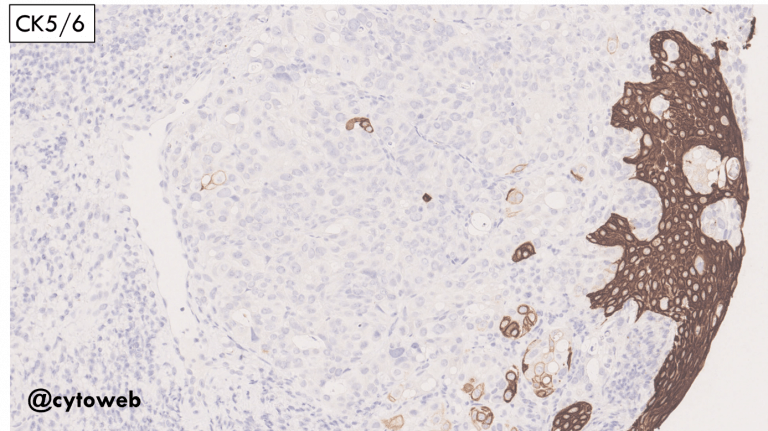

The malignant cells show features of adenocarcinoma.

- Metastatic malignancy: This is the favoured diagnosis as a second distinct population of benign thyroid cells are admixed with the carcinoma (see below).

Possible primary sources of a metastatic adenocarcinoma to the thyroid to consider:

- Lung adenocarcinoma

- Renal cell carcinoma (not likely the clear cell type)

- Breast carcinoma (invasive carcinoma of no special type)

- Gastrointestinal tract/pancreatobiliary adenocarcinoma

Knowledge of relevant clinical history and immunocytochemistry on cell block would be very helpful in the DDx.